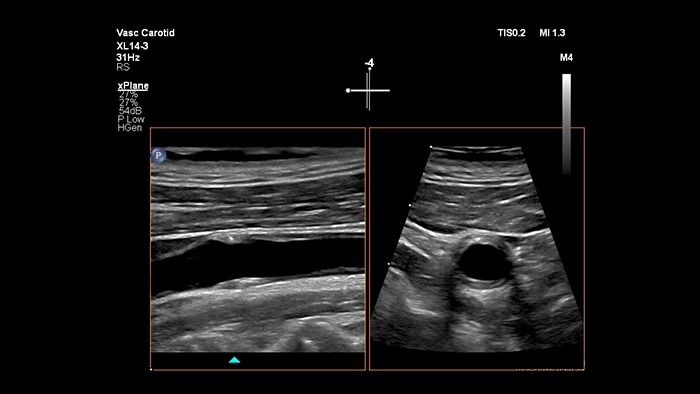

Imágenes xPlane

El transductor XL14-3 xMATRIX ofrece una adquisición de imágenes xPlane que supera al sistema convencional para exploraciones vasculares, pues ofrece imágenes en tiempo real tanto en los planos longitudinal como transversal de forma simultánea. La ventaja principal: las imágenes xPlane eliminan la necesidad de girar el transductor para adquirir vistas ortogonales. Basta con mover la esfera para realizar una evaluación anatómica completa, con lo que se ahorra tiempo en la exploración.